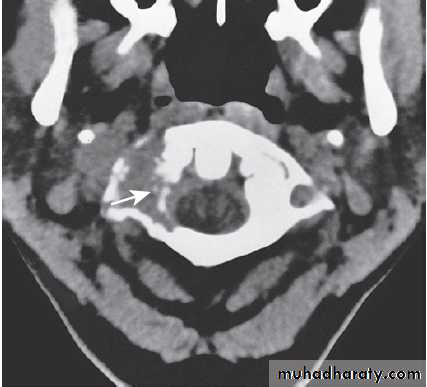

Different techniques of imaging the cervical spine. A Lateral X-ray showing bilateral C6/7 facet dislocation. B Myelogram showing

widening of cervical cord due to astrocytoma (arrows). C MRI showing posterior epidural compression from adenocarcinomatous metastasis to the posterior arch of T1 (arrows).